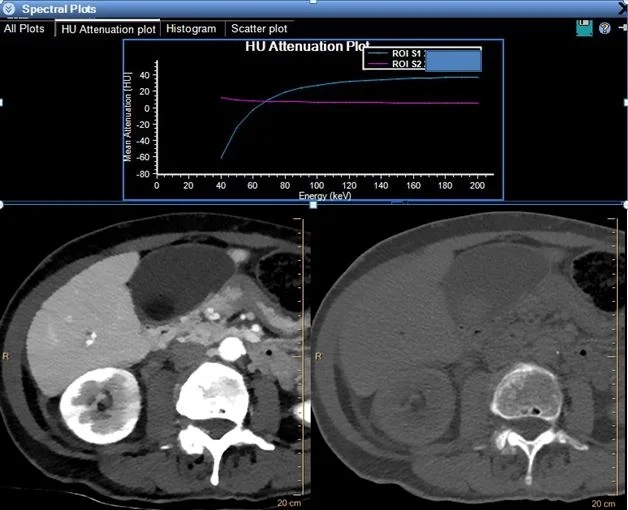

Behavior of gallstone and bile on spectral analysis is quite different. The curves intersect at about 70 keV, which is typical energy of conventional CT scan. Gallstones (blue curve) are strikingly hypodense on low energy relative to bile (magenta c…

Behavior of gallstone and bile on spectral analysis is quite different. The curves intersect at about 70 keV, which is typical energy of conventional CT scan. Gallstones (blue curve) are strikingly hypodense on low energy relative to bile (magenta curve, also image on left) and high density on higher energy (image on right).